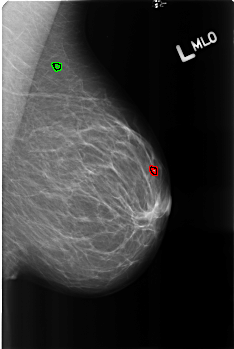

B_3165_1.LEFT_MLO

LEFT_MLO LINES 4528 PIXELS_PER_LINE 3032 BITS_PER_PIXEL 12 RESOLUTION 50 OVERLAY

FILE: B_3165_1.LEFT_MLO.OVERLAY

TOTAL_ABNORMALITIES 2

ABNORMALITY 1

LESION_TYPE CALCIFICATION TYPE LUCENT_CENTER DISTRIBUTION N/A

ASSESSMENT 2

SUBTLETY 4

PATHOLOGY BENIGN_WITHOUT_CALLBACK

TOTAL_OUTLINES 1

BOUNDARY

ABNORMALITY 2